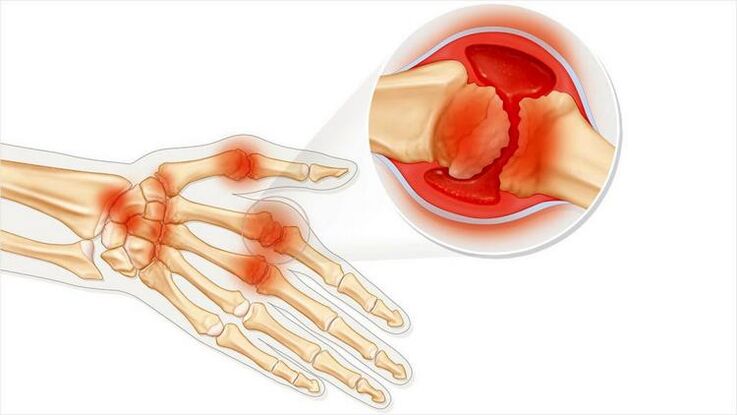

Gelenkarthritis ist eine Erkrankung der Gelenkentzündung. Äußert sich hauptsächlich durch Schwellung und Rötung. Die innere Auskleidung des Gelenks wird zerstört, was zu Schmerzen führt, die oft nur schwer erträglich sind.

Arthritis ist durch folgende Merkmale gekennzeichnet:

- Wenn die Haut in der Nähe des Gelenks rot wird, kann Fieber auftreten.

- Veränderung des Gelenkbildes.

- Tumor.

- Schmerzhafte Empfindungen beim Bewegen.

- Unangenehme Empfindungen beim Drücken auf ein Gelenk.

- Arthritis kann eine Infektionskrankheit sein. Dann treten alle Symptome auf, die einer Infektion entsprechen: Unwohlsein, Fieber, Schüttelfrost.

Arthritis kann ein einzelnes oder mehrere Gelenke betreffen. Sie tritt mit akuten Schmerzen oder schleichend auf und verursacht eine chronische Erkrankung. Dann tritt ein dumpfer, schmerzender Schmerz auf.